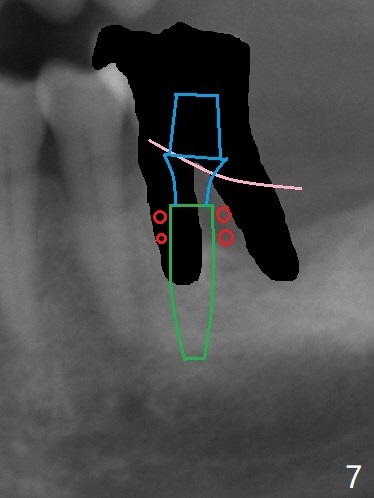

A 56-year-old man had distal gingival erythema at #19 with a fistula (Fig.1). Upon opening the pulpal chamber, the pulp is vital in the mesial canals, while necrotic distal. Root canal therapy is finished 1.5 months later (Fig.2). Although the patient was pleased with the treatment, the gingival infection and fistula did not improve. The tooth mobility increases over the years (Fig.3). He will return for evaluation next Monday. What should be done?